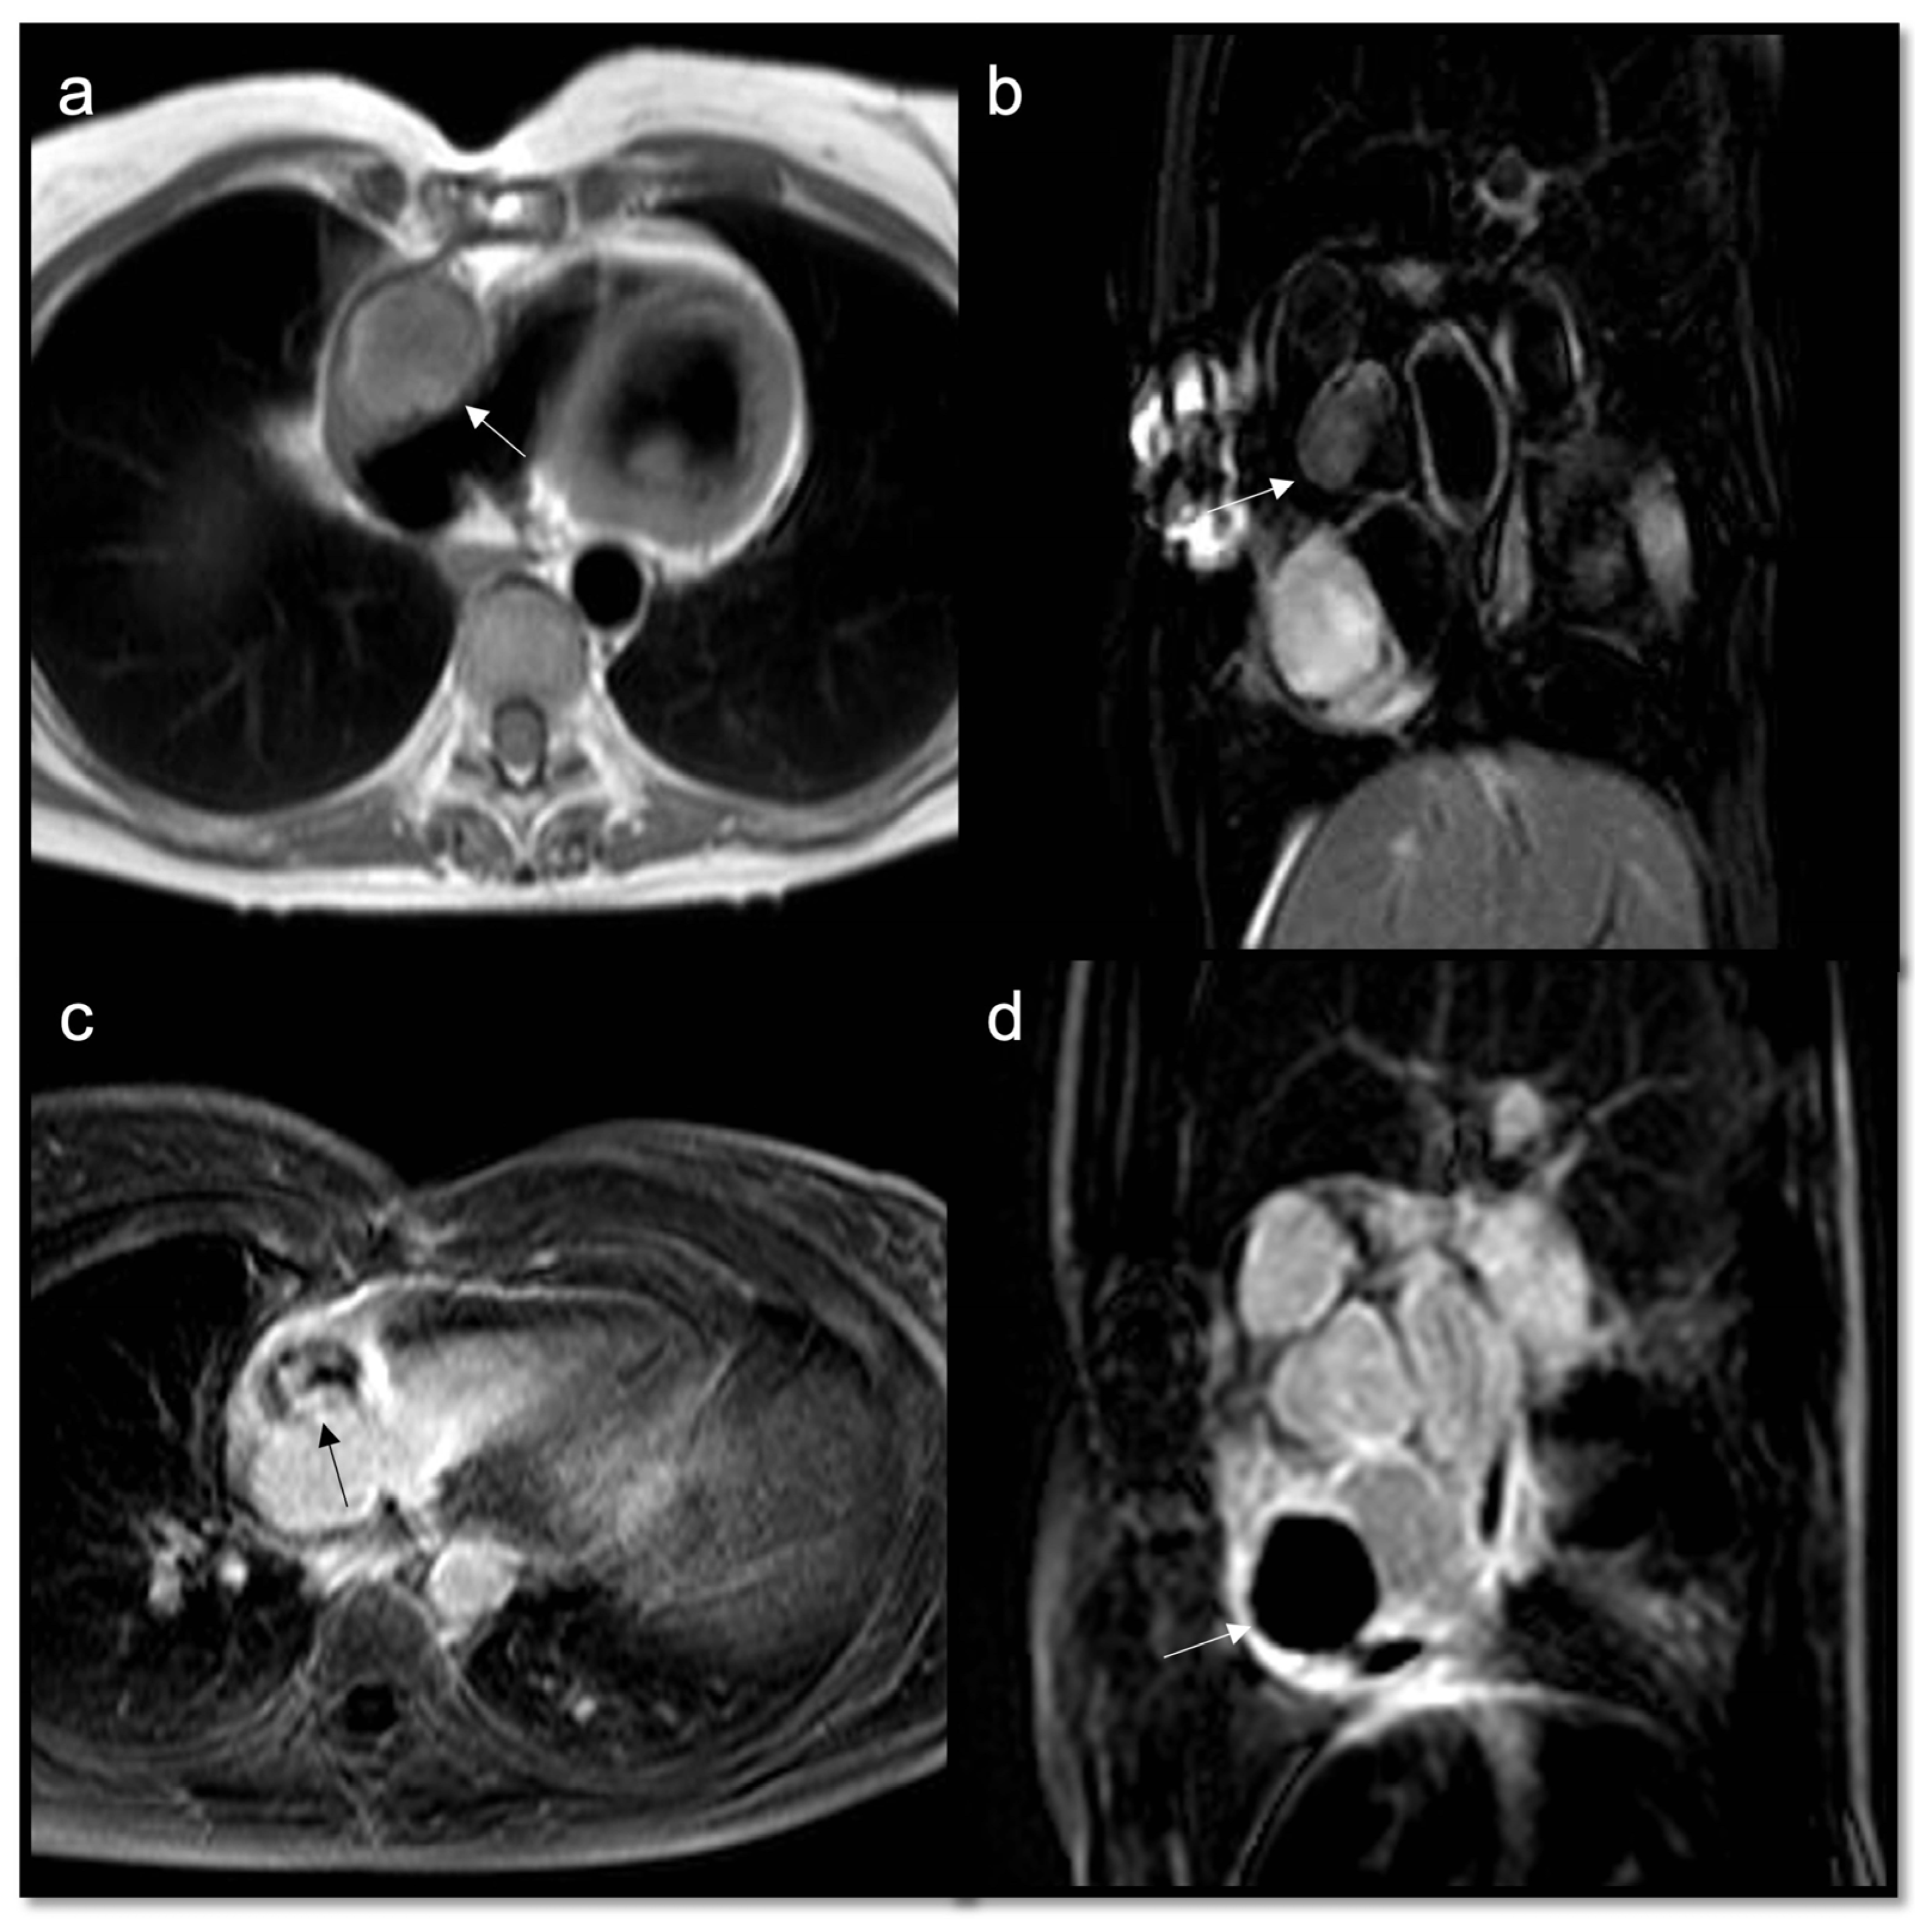

- To recognize fluid content such as a pericardial cyst or myocardial cyst (Figure 3)